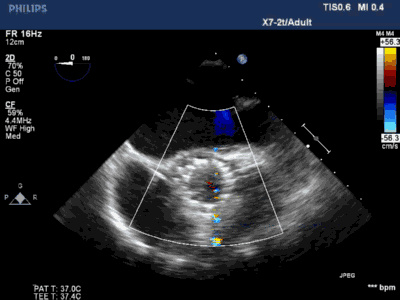

术前心超:

双平面示type 1型二叶瓣